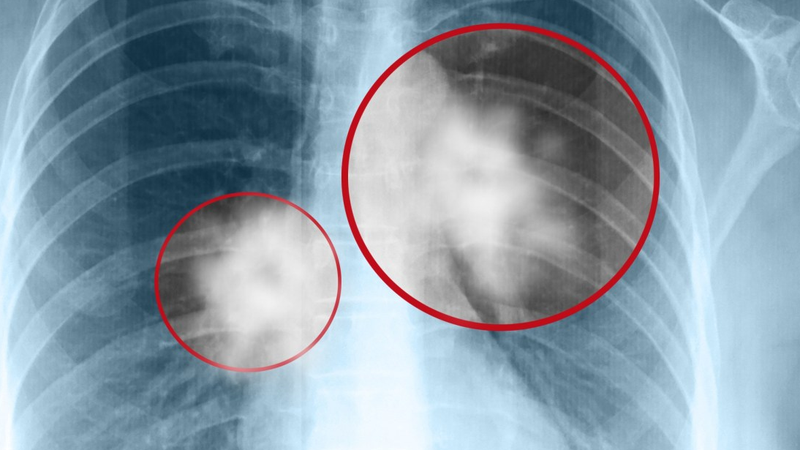

- Chụp Xquang phổi thẳng, là xét nghiệm đầu tiên và rất cần thiết vì nó cung cấp rất nhiều thông tin về bệnh và những bệnh đi kèm: hình ảnh X Quang đặc hiệu thường thấy trên phim là hình một khối tròn, đặc, nằm trong một hang lao có hình cầu hoặc hình bầu dục, hình tròn đặc này thay đổi theo tư thế của bệnh nhân mà giới chuyên môn gọi là hình lục lạc. Với phim chụp phổi thông thường cho phép chúng ta chẩn đoán xác định đến 90% các trường hợp.

- Chụp Xquang với máy điện toán cắt lớp còn gọi là chụp CT, dùng để xác định rõ u nấm trong một số trường hợp gặp phải khó khăn trong chẩn đoán và khám lâm sàng và Xquang phổi thông thường.